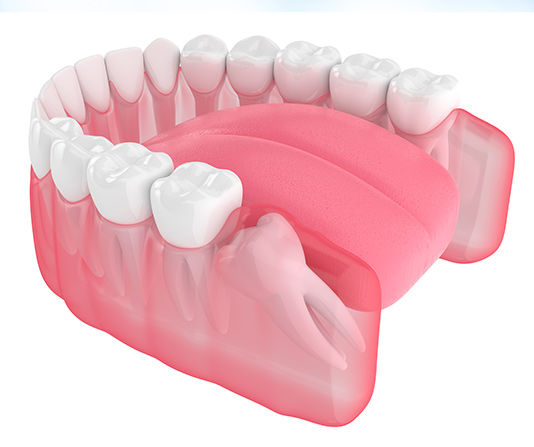

Sometimes a wisdom tooth will emerge sideways or tilted from the gum.